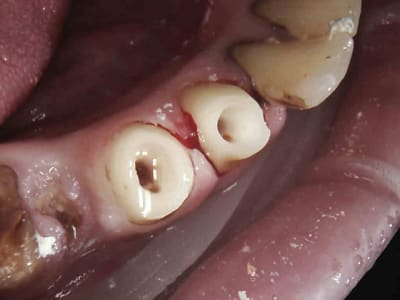

Les 4 en une heure et quart pulpec, taille, empreinte, provisoires. Tarif CMU, rentable ! -)))))

4 zvkifx - Eugenol

5 obhiok - Eugenol

7 ix4kkx - Eugenol

8 kloqft - Eugenol

9 sugvfe - Eugenol

Images jm2g2g - Eugenol

le petit coup de faucille sur la 45 valait bien 30 balles quand meme =)